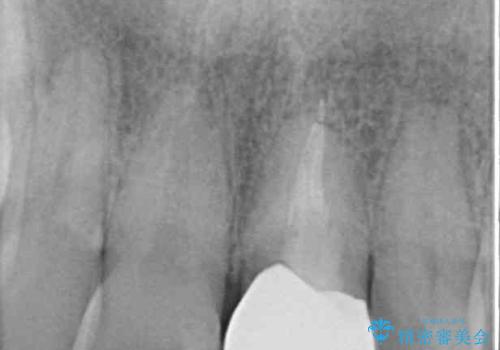

下顎は左右1本ずつ小臼歯が欠損しており、右側にはやや大きな欠損がありました。

欠損により下顎歯列は相対的に小さく、上顎に深く咬みこんでしまうディープバイトとなっていました。

インプラントの埋入は矯正治療中に行い、矯正治療後はインプラント上補綴および、前歯のセラミック治療を行いました。